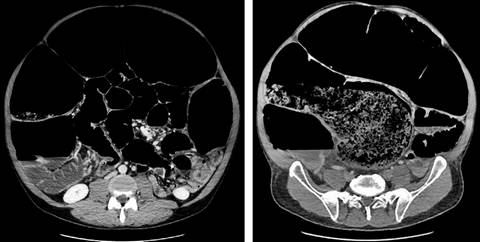

En la primera gasometría resulta llamativa la escasa afectación del equilibrio ácido-base (pH 7.4, PCO2 40.4 mmHg, CO3H- 28.3 mEq/L) e iónico (K+ 3.4, Na++ 135, Ca++ 1.10, Cl- 97), aunque presenta hemoglobina 16.4 g/dL y lactato 3.8 mmol/L. La analítica muestra 520,000 plaquetas/µL, sin afectación renal (urea 51 mg/dL, creatinina 1.16 mg/dL) ni trastornos de la coagulación (INR [International Normalized Ratio] 1.16, TTPAratio [Tiempo De Tromboplastina Parcial Activado-Relación] 1.11). La tomografía axial computarizada (TAC) muestra un gran fecaloma en ampolla rectal que provoca dilatación significativa colorrectal (16 cm en colon transverso y 13 cm en ciego) de íleon y yeyuno distal (Figuras 2 y 3). El estómago e intestino delgado proximal están colapsados y no existe neumoperitoneo ni líquido libre intraabdominal.

Valorado por Cirugía General, se desestima actitud quirúrgica urgente optando por manejo conservador con enemas y extracción manual. Ante la inefectividad de este tratamiento se recurre a realizar colonoscopía, consiguiendo desimpactación parcial y colocación de sonda larga rectal. En este contexto, el paciente presenta deterioro a nivel respiratorio de tipo restrictivo atribuido a la gran distensión abdominal, por lo que se realiza nueva TAC, que muestra imágenes de neumatosis intestinal en colon izquierdo. Ante la refractariedad a las medidas conservadoras y el empeoramiento clínico-radiológico, el Servicio de Cirugía General indica laparotomía de emergencia 36 horas después de la llegada del paciente al hospital. En ese momento se informa al Servicio de Anestesiología de la existencia y situación clínica del paciente, que aún permanece ingresado en el área de Urgencias.